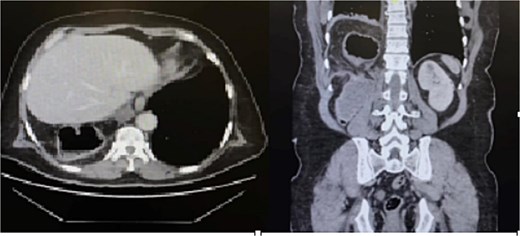

The patient was initially resuscitated with intravenous fluids. An urgent abdominal computed tomography (CT) scan was performed, revealing a herniated and obstructed segment of large bowel loops with mesenteric fat at the hepatic flexure, likely through the posterior right hemidiaphragm (Fig. 1). The scan showed a proximally dilated cecum and ascending colon, with a transitional zone observed at the neck of the hernia, leading to a distally collapsed colon. Additionally, there was an area suspicious for pneumatosis intestinalis within the obstructed bowel segment, along with adjacent fat stranding and free fluid—findings that raised concerns for strangulation or early ischemia. The scan also indicated a right-sided pleural effusion and adjacent atelectasis (Fig. 2).

CT scan of the thorax revealed a right-sided pleural effusion and adjacent atelectasis.